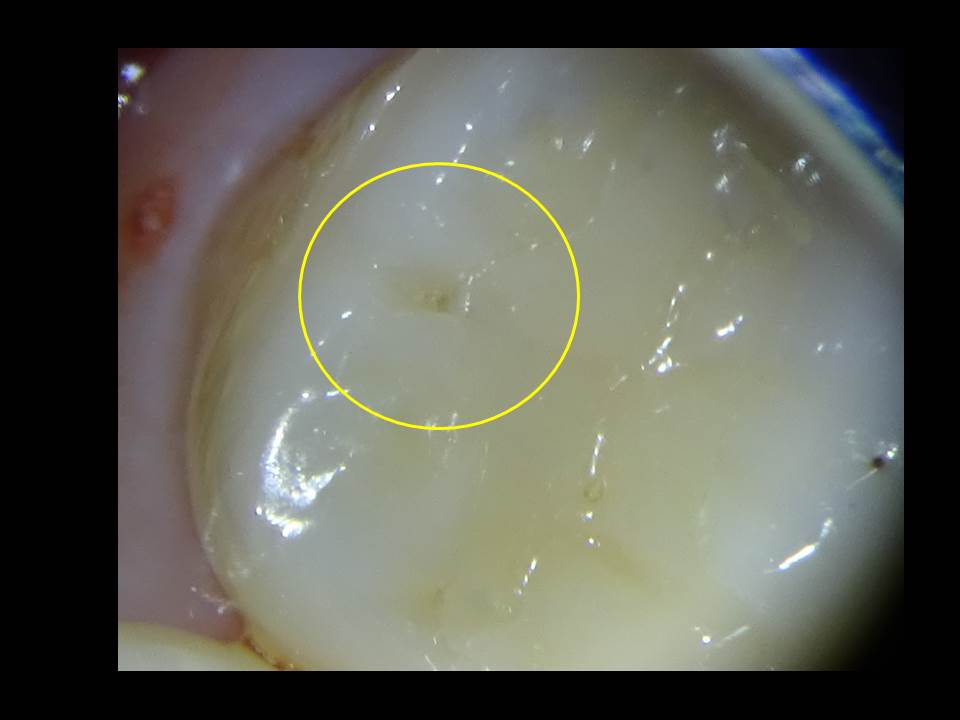

「上の奥歯がチョコレートを食べたらしみる、何かが欠けた気がする」

ということで、来院された患者様でした。

一見何もなさそうな感じですが、、、

咬む面に冷たい風を当てたところ、一番右の歯に痛みがありました。

マイクロスコープ(歯科用顕微鏡)を覗いてみて、20倍まで拡大すると、

確かに古い詰め物が欠けており、穴が開いていました。

一部その中には虫歯もあり、この画像を事前に患者様にもお見せし説明したところ、納得され、安心して治療に入ることができました。

幸いにも虫歯は中でさほど大きくは広がっていなかったため、マイクロスコープ(歯科用顕微鏡)下で、健康な歯は削らないよう丁寧に除去した後、コンポジットレジン(歯科用のプラスティック)をつめて、1回で終了。